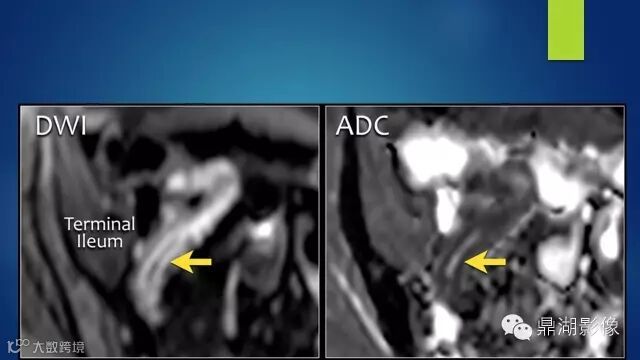

The comb sign refers to the hypervascular appearance of the mesentery in active Crohn disease.

Fat halo aslo can be seen in normal terminal ileum.

It is the comb sign the most specific sign for crohn's disease.